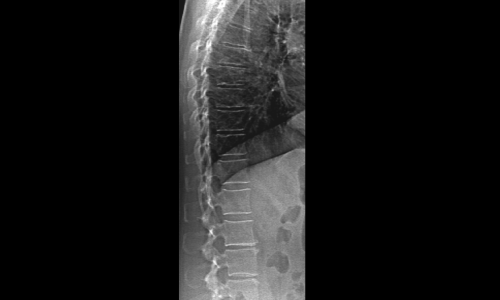

Grazie al nuovo detettore e al nuovo generatore ad alta frequenza e a doppia energia è possibile ottenere immagini altamente dettagliate e ad alta risoluzione per tutte le tipologie di pazienti, con una dose minima di radiazioni (solo 1% della dose utilizzata dai più comuni apparecchi).

Inoltre la tecnologia ‘Fan Beam’ del sistema Horizon consente di catturare immagini del femore e della colonna vertebrale in appena 10 secondi riducendo dell’85% i tempi di analisi.